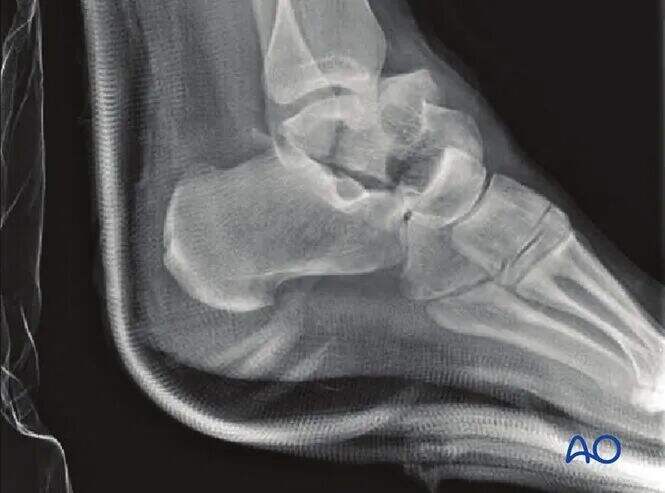

Nezamaknjeni zlomi morda zahtevajo le preproste rentgenske posnetke, vendar je ta primer redko; večina zlomov vratu talusa ima vsaj nekaj stopnje zamika.

CT slikanje je neprecenljivo, kadar obstaja dvom o premiku zloma ali kadar je potrebno odstraniti okostnico subtalarne sklepa. Pri hujših poškodbah običajno velja, da večji premik nakazuje hujšo osteohondralno poškodbo subtalarne in tibiotalarne sklepa. Takšni zlomi pogosto zahtevajo kirurško odstranitev okostnice in fiksacijo.